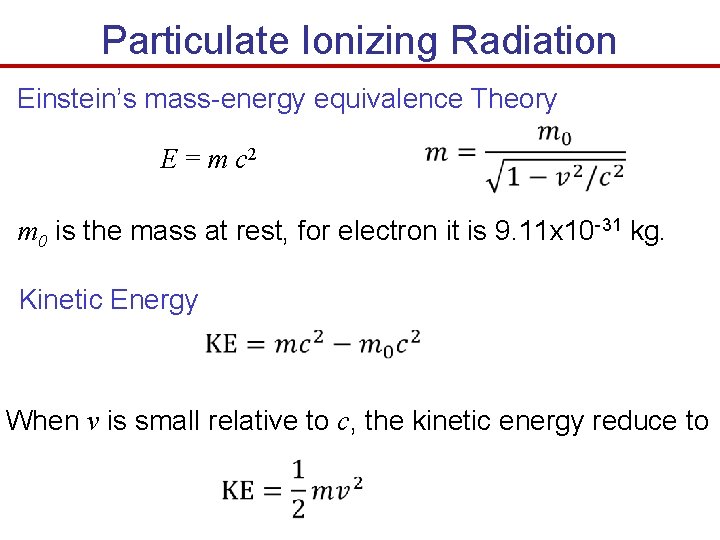

Particulate Ionizing Radiation Einstein’s mass-energy equivalence Theory E = m c 2 m 0 is the mass at rest, for electron it is 9. 11 x 10 -31 kg. Kinetic Energy When v is small relative to c, the kinetic energy reduce to